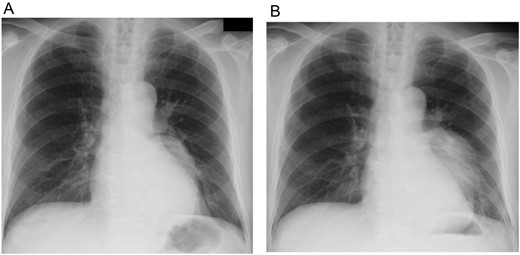

A 74-year-old man was referred to our hospital after a left middle and posterior mediastinal tumor was detected on computed tomography (CT) performed as an examination for dry cough in other hospital. CT about 2 years earlier had shown a 3.2 × 2.4-cm lipomatous tumor at the left hilum adjacent to the left lower pulmonary vein (Fig. 1), and that lipomatous tumor was considered the origin of the present mediastinal tumor. Contrast-enhanced CT performed in our hospital showed a heterogeneous tumor, displacing the left lower lobe of the lung, and measuring 10 × 7.4 × 6 cm on horizontal and coronal sections (Fig. 2A and B). Magnetic resonance imaging showed a hyperintense marginal region with central hypointensity on T1-weighted imaging, and heterogeneously high intensity in the whole tumor on T2-weighted imaging. We scheduled surgical resection, and the patient was admitted to our hospital 3 weeks after the first visit. Chest radiography showed rapid growth of the left intrathoracic tumor (Fig. 3A and B), and CT revealed a tumor measuring 11.4 × 8 × 6.2 cm without pleural effusion or hemothorax.

Chest X-ray from the first visit to our hospital (A), and 3 weeks after that initial visit (B). These photos show rapid growth of the left intrathoracic tumor.